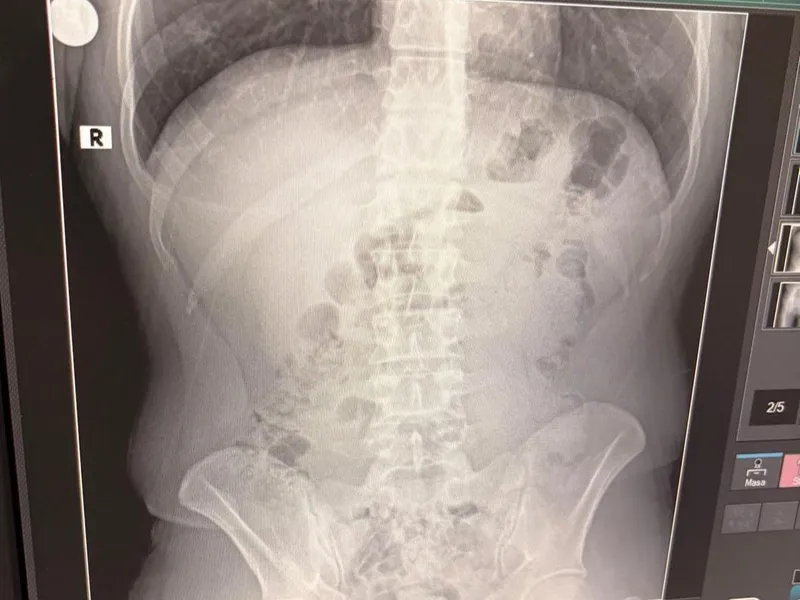

Adreste yapılan arama sırasında ekipler, şüphelilerden birinin üstünde 1 adet kapsül ele geçirdi. Şüphe üzerine tüm şüpheliler hastaneye götürüldü ve yapılan röntgen kontrollerinde 3 kişinin midelerinde kapsül içine gizlenmiş metamfetamin tespit edildi.

Hastanede tedavi altına alınan şüphelilerin vücudundan kapsüller çıkarılırken, adreste ele geçirilenlerle birlikte toplam 1 kilo 516 gram metamfetamin ele geçirildi.